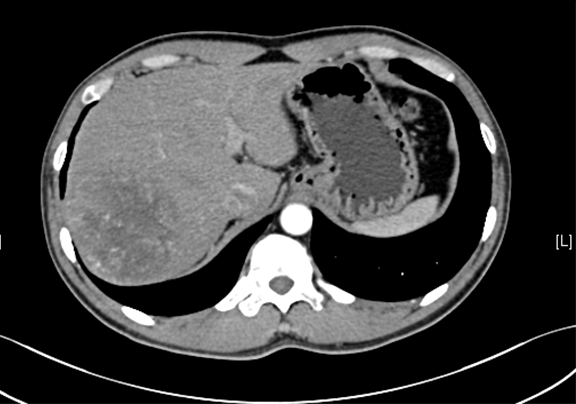

术前CT检查:

静脉期

下腹部增强CT示:肝右后叶占位性病变,考虑肝癌可能性大。